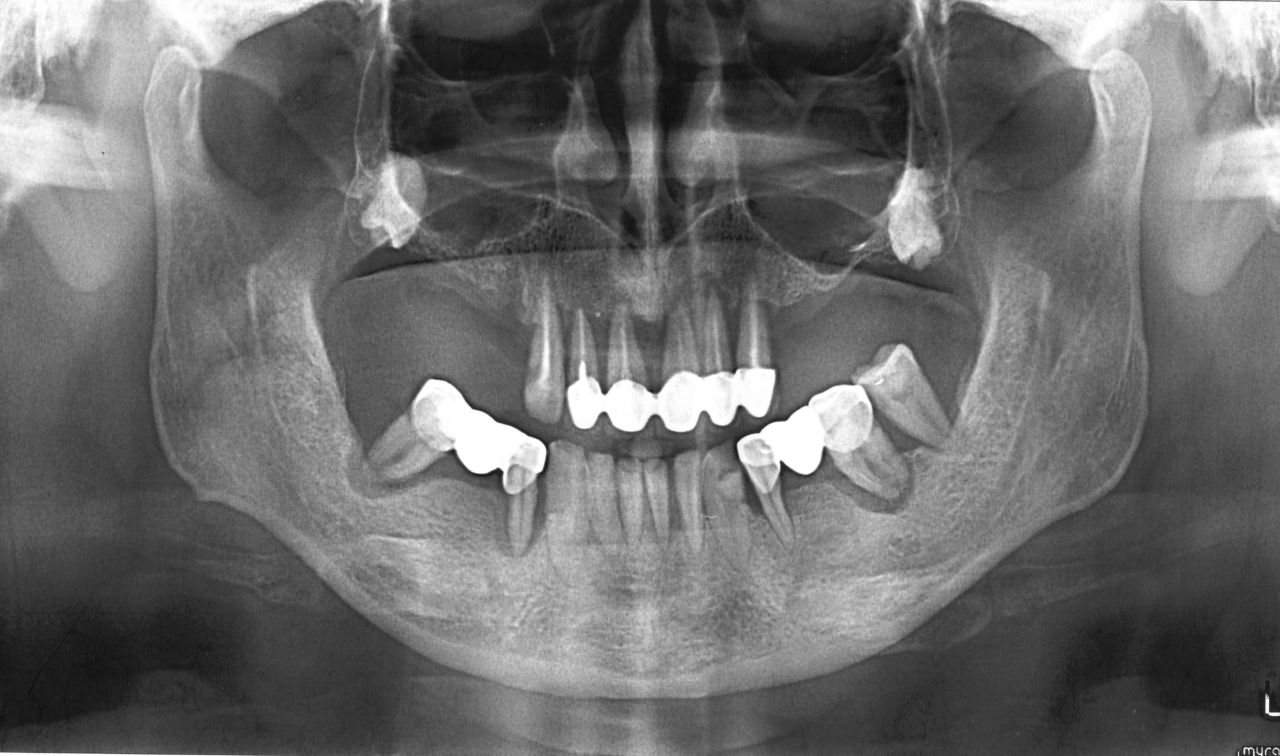

Петрович Опубликовано 26 марта, 2019 Поделиться Опубликовано 26 марта, 2019 Мой дядя.Хочет зубы сохранить.Но тут похоже что будет ПСПП Ссылка на комментарий

chervoncevdaniil Опубликовано 26 марта, 2019 Автор Поделиться Опубликовано 26 марта, 2019 Да,в таких случаях всегда непросто объяснять,вроде во рту полно зубов,а удалять придется все Ссылка на комментарий

Петрович Опубликовано 26 марта, 2019 Поделиться Опубликовано 26 марта, 2019 (изменено) Да,в таких случаях всегда непросто объяснять,вроде во рту полно зубов,а удалять придется всеПравда и зубы ему уже надоели. Шатаются. Воспаляются. Но какие-то жуёт. И без чспп сразу на пспп сложно будет. Нижние клыки может все таки оставить. Изменено 26 марта, 2019 пользователем Петрович Ссылка на комментарий

chervoncevdaniil Опубликовано 26 марта, 2019 Автор Поделиться Опубликовано 26 марта, 2019 Правда и зубы ему уже надоели. Шатаются. Воспаляются. Но какие-то жуёт. И без чспп сразу на пспп сложно будет.Нижние клыки может все таки оставить.Годика на 3 в лучшем случае,частичка их дораскачает за это время Ссылка на комментарий